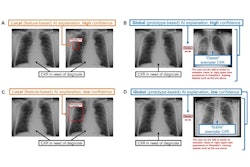

Chest-CAD is a deep-learning algorithm approved by the U.S. Food and Drug Administration in 2021. The software identifies suspicious regions of interest (ROIs) on chest x-rays and assigns each ROI to one of eight clinical categories consistent with reporting guidelines from the RSNA.